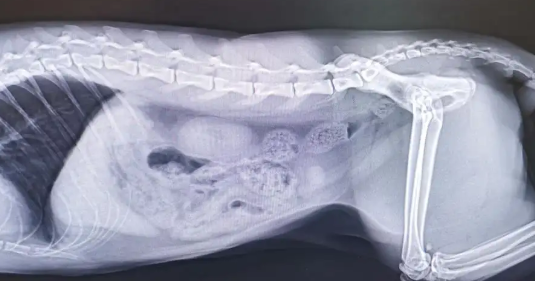

但是如果猫已经两天没有排尿了,说明尿结石比较严重,这个时候需要就医导尿,冲刷猫的尿道。

每天一包肾石通颗粒,多次喂食,连续喂食七天。此外,阿莫西林拉维酸钾早晚连续喂食三天。当猫可以拉出一些尿液时,每次可以用30~40毫升的水冲洗。对于小便困难的猫来说,每次服用的水量可以上升到60毫升。如果猫体质好,基本上喂五天左右就能正常小便。